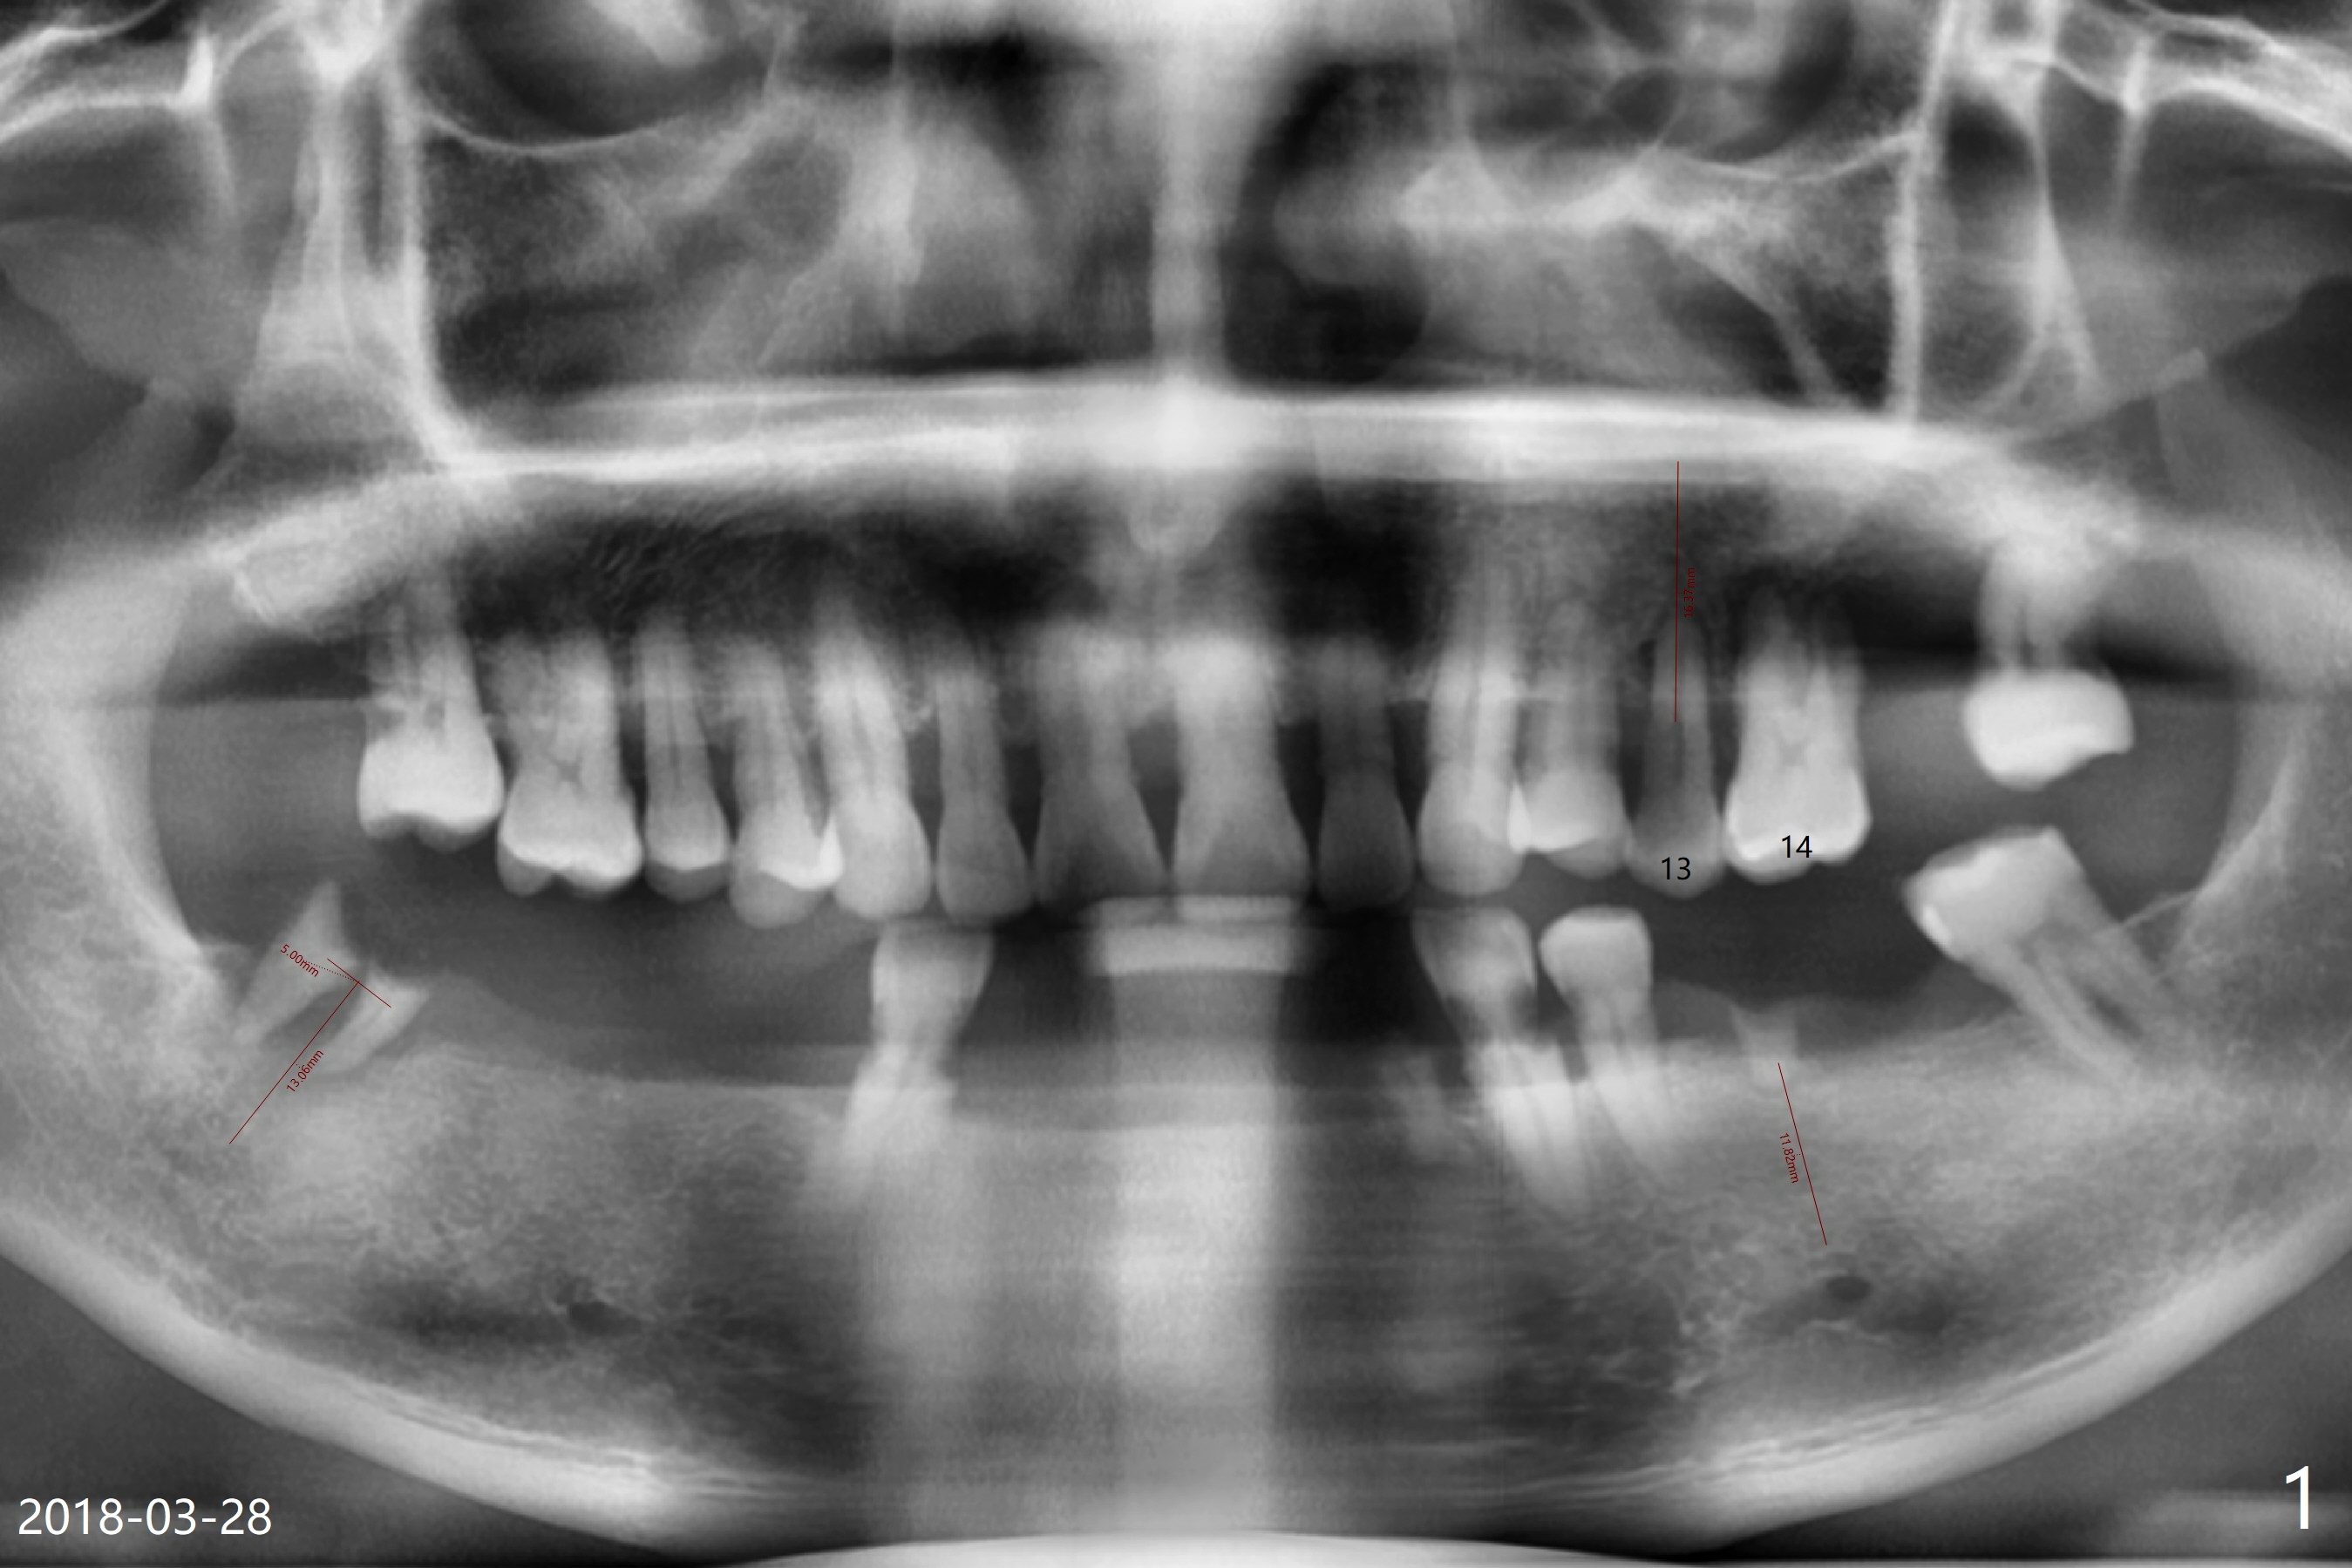

60岁男两年中牙齿状态变化大(图一,二)。上颌深洗时,只同意拔除左上第一磨牙,后者腭侧(图三P)和远中颊侧(DB)牙槽窝特别浅,而近中颊侧大而深(MB),需要做位点保留吗?只在近中颊侧窝做?